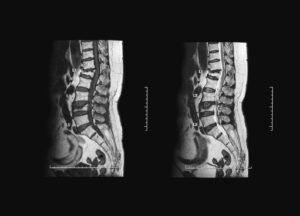

Как изглежда спиналната стеноза на MRI

MRI изследването е едно от най-често използваните образни изследвания при съмнение за спинална стеноза. То позволява да се видят подробно междупрешленните дискове, нервните структури и пространството в гръбначния канал.

При MRI спиналната стеноза може да се прояви като:

стеснение на гръбначния канал

намалено пространство около нервните коренчета

дискова протрузия или дискова херния

остеофити

удебелени връзки

промени във фасетните стави

Образното изследване дава важна информация за структурата на гръбначния стълб, но винаги трябва да се разглежда заедно със симптомите на пациента.